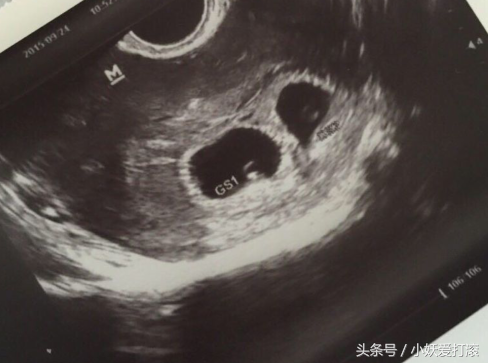

27天去B超检查,显示是双胞胎,胎心胎芽都有了,我是属于晚婚,31岁才结婚,33岁做试管婴儿,没想到过程这么顺利,还给了我一对双胞胎,感谢我老公和婆婆一直鼓励我,一直支持我,没有给我压力,而且怕我疼,我婆婆跟我说太疼就不要做了,回来领养一个,也是一个样的。

到第二次取卵的适合,有七个卵泡,都取出来了,配对了五个,我们都很开心,然后过了三天移植了两枚胚胎。期间我一直吃蛋白粉和牛奶豆浆。移植的过程很顺利,感觉一分钟就搞定,我在床上躺了几天,很少下床,然后过几天后去抽血,医生告诉我有了,我给高兴的还问医生有没有可能是双胞胎,医生还让我不要太贪心。27天B超检查显示是双胞胎,感谢感恩。